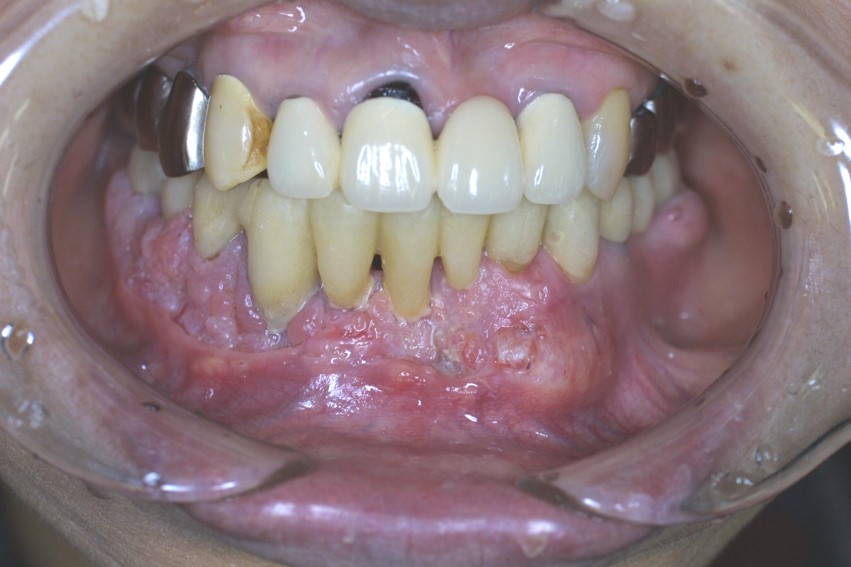

進行がん:歯科、耳鼻科などで大丈夫と言われ痛みが出るまで放置していた症例

顎(あご)が腫れて義歯(入れ歯)が合わなくなったり、違和感(変な感じ)がある

入れ歯をしている方で、がんなどのできものにより、入れ歯が合わなくなり、噛みづらいなどの訴えをされる方がいます。